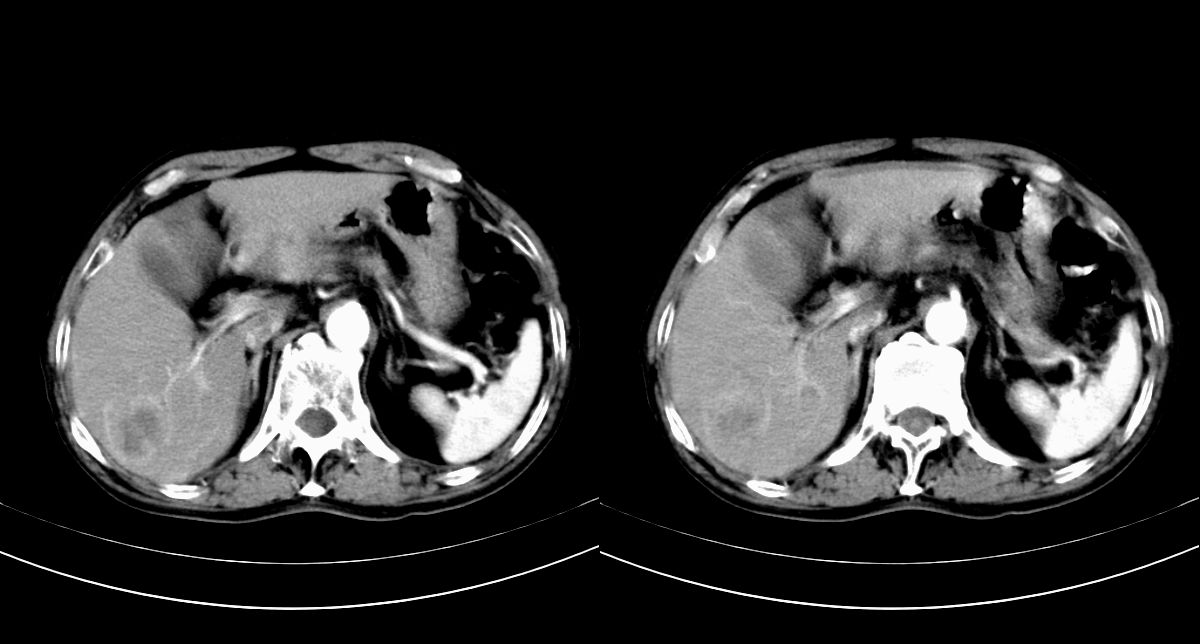

男,79y,无不适。体检发现肝脏占位。

肝内多发低密度结节,增强动脉期明显强化,门脉期逐渐下降,内有液化坏死区。

诊断:

肝细胞癌(结节型)

鉴别:肝转移癌。

肝内多发低密度结节灶,增强动脉期明显不规则环状强化,;门脉期逐渐下降,肿瘤壁厚薄不一,内有坏死液化区。

诊断:肝转移癌可能

鉴别:1原发性肝癌(强化方式符合,建议查afp)

2肝脓肿(无临床病史支持)

诊断:典型的肝转移癌